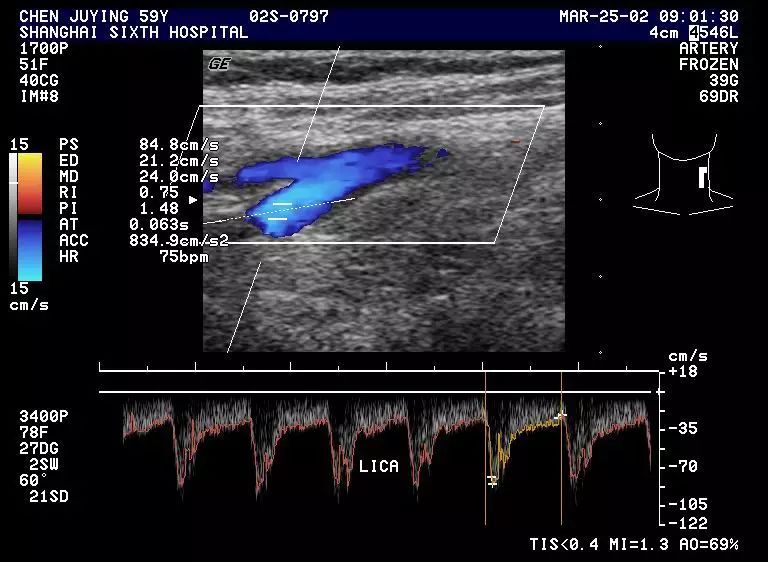

(2) 正常颈内动脉显示低阻型血流频谱,收缩期血流速上升缓慢,双峰间切迹不明显,呈三峰递减型或二峰型,全舒张期均显示流速较CCA为高,尤高于ECA。

1.2 正常颈内动脉频谱